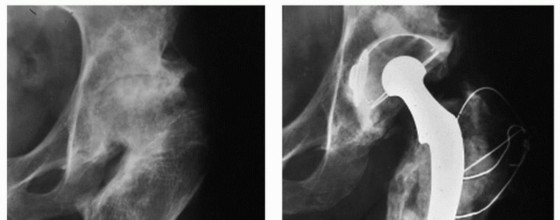

توضح هذه الصور حالة مريض يعاني من تشوه سابق في الفخذ القريب، حيث لم تسمح التقنيات الجراحية القديمة بتصحيح التشوه بشكل كامل، مما أدى إلى وضع مكون الفخذ في موضع غير مثالي وتسبب في ارتخاء الزرعة لاحقاً. هذا يؤكد أهمية التخطيط الدقيق والتقنيات الحديثة التي يتبعها الأستاذ الدكتور محمد هطيف.